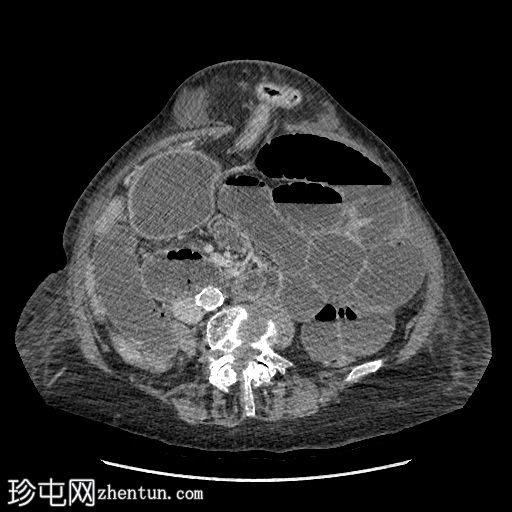

轴位增强扫描(门静脉期)

可见一大型上腹疝,内含部分结肠,矢状位图像亦可见。

另可见一小型右侧闭孔疝,内含脂肪。冠状位图像亦可见。

未发现胸腹部恶性肿瘤。